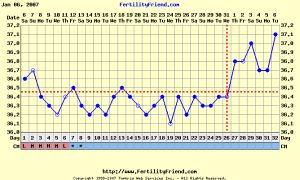

Ma elkezdtem barnázni, bár már tegnap este is volt egy csepp, azt hiszem ma délutánra meg is jön. Erről a hónapról is ennyit. Voltam természetgyógyásznál, aki felsorolta, hogy mi bajom van. Félelmetes volt, hogy mindenben igaza volt, ami betegségről tudtam. Bár ez nem azt jelenti, hogy visszamegyek hozzá. Ja és közölte velem, hogy endom van, úgy, hogy én nem szóltam neki semmit.

Na hát ettől teljesen kész voltam. Felírt egy csomó természetbogyót egy kisebb vagyonért és azt mondta szeptemberre ott lesz a baba a pocakomba, addigra elmulasztjuk az endot. Gondoltam magamban, ha tényleg az van, amit ugye csak laparral lehet megállapítani akkor mit kínlódnak vele oly sokan, és csak ilyen bogyókkal el lehet tüntetni? Természetesen nem vettem semmit, de ezt azután döntöttem el, hogy mondtam, szedek aloe verás készítményeket és kérdeztem tőle, hogy az nem jó? Erre: de az is jó csak ez a másik hatásosabb. Egy tanácsát viszont megfogadtam elmegyek egy 3D-s UH-ra (hasi és kismedencei) aztán ha hazajöttünk Beneluxból befekszem a kórházba. Bár halkan jegyzem meg, hogy szerintem is endom van és azért nem jön össze, és a stressztől ami benne van. Kedden megyek a UH-ra hát nagyon kiváncsi leszek, állítólag a megvastagodásokat szépen mutatja és lehet következtetni, hogy hol van az endo, ha van. A Hattyúházban van ez a magánrendelő és sok kismami jár oda.